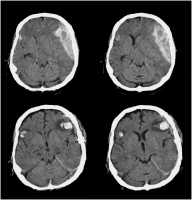

Epiduralhämatom

Abbildung 4: 5-jähriges Kind mit akutem Epiduralhämatom 1 Stunde, 3 Stunden und 8 Stunden nach Trauma